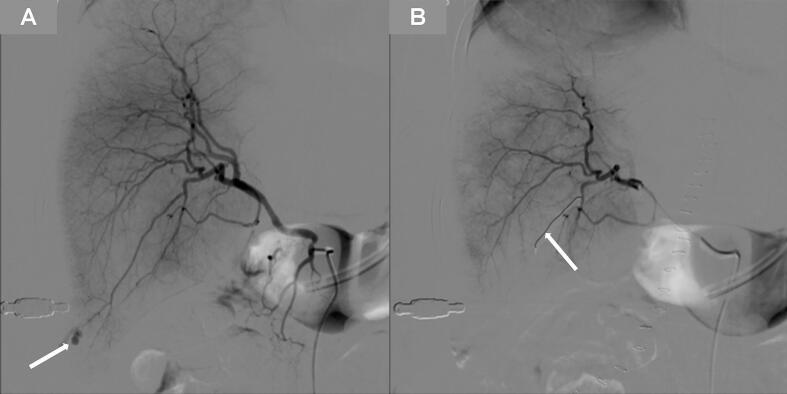

We present the case of a 35-year-old pregnant woman who developed worsening pain under the xiphoid process the night following a cesarean section. Her blood pressure dropped from 189/110 mmHg to 90/60 mmHg within 40 min. Vaginal exploration revealed no blood flow, and subsequent laparotomy uncovered multiple small liver surface lacerations actively bleeding. Emergency transcatheter arterial embolization (TAE) was promptly performed, stabilizing her condition. She was discharged 37 days post-admission.

TAE plays an important role in the treatment of HELLP syndrome with spontaneous liver rupture, with characteristics of minimal trauma and good efficacy, but the evidence supporting this recommendation is somewhat limited.

This case underscores TAE as a potentially effective and less invasive alternative to surgical interventions for managing HELLP syndrome with spontaneous liver rupture. Further research is needed to better clarify the safety and efficacy of TAE in the treatment of HELLP syndrome with spontaneous liver rupture.